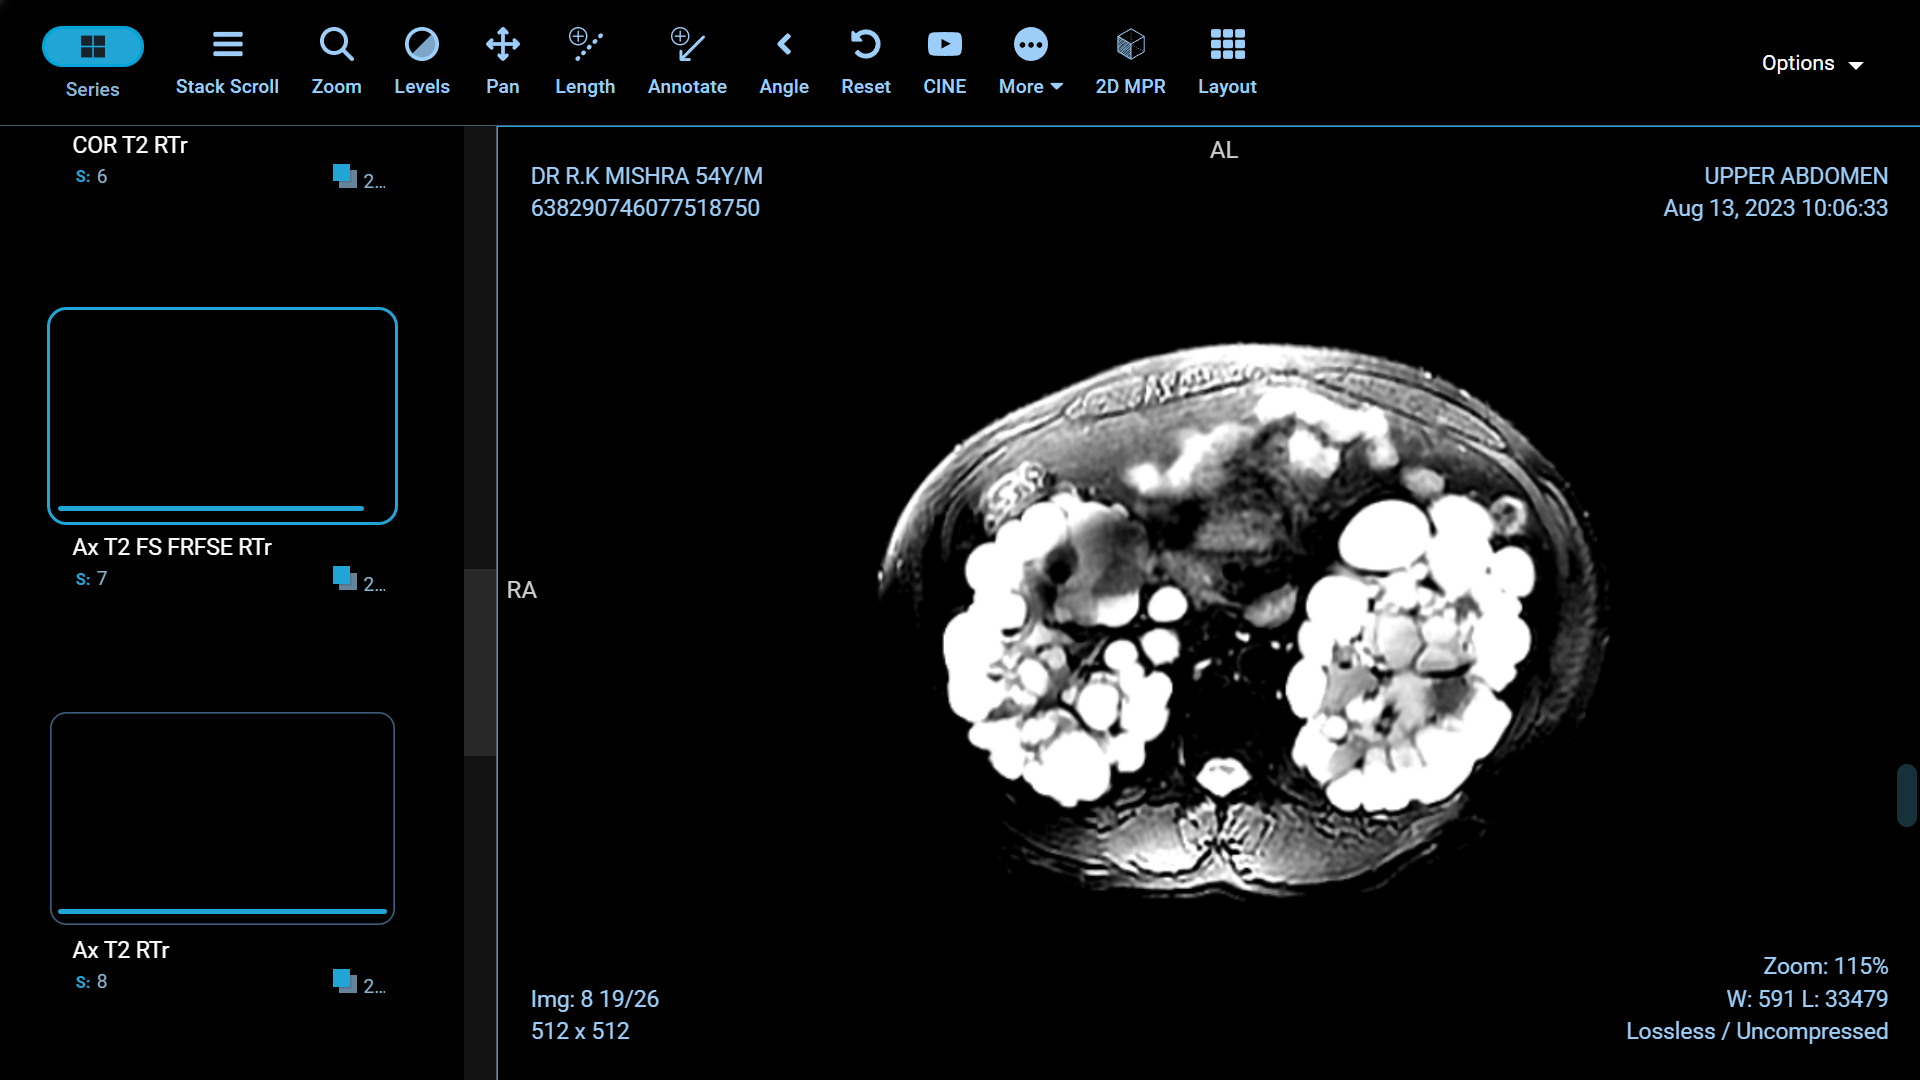

Polycystic Kidney Disease (PKD) is a genetic disorder characterized by the formation of fluid-filled cysts in the kidneys, which can lead to renal failure if left untreated. Fortunately, recent advancements in medical science have paved the way for more effective treatments and improved the quality of life for those affected by this condition. In this article, we will explore some of the groundbreaking innovations in PKD treatment.

Foam sclerotherapy is a medical procedure that involves injecting a specialized foam directly into kidney cysts. The foam is made by mixing a liquid sclerosing agent, typically a solution of alcohol or polidocanol, with air or gas to create a stable, persistent foam. This foam is then injected into the cyst through a thin needle under ultrasound or CT guidance.

The success of foam sclerotherapy lies in its ability to cause intentional injury to the cyst lining, promoting inflammation and scarring. This process leads to the collapse and sealing of the cyst, preventing further fluid accumulation and reducing the cyst's size.

Minimally Invasive: Foam sclerotherapy is a minimally invasive procedure, which means it typically requires only a small incision or needle puncture. This reduces the risk of infection, pain, and complications associated with more invasive surgical procedures.

Preservation of Healthy Kidney Tissue: Unlike some other treatments, foam sclerotherapy specifically targets the cyst, leaving the surrounding healthy kidney tissue intact. This is particularly important for individuals with only one functioning kidney.